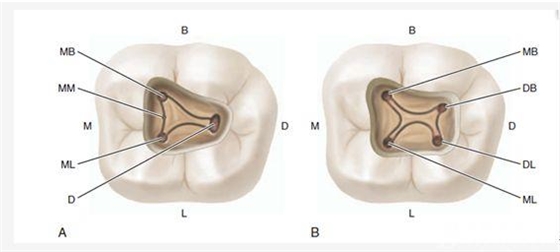

H、關于下磨牙MM根管的重視問題:

D、“中心平衡對稱法則”:主根管在牙根中的分布符合“中心平衡對稱法則”,牙齒在進化過程中,跟其它大自然的規(guī)律一樣,即根管基本位于牙根橫斷面的中心,類似于髓室也是(或者鈣化前曾經(jīng)也是)位于牙冠橫斷面的中心一樣,如果你發(fā)現(xiàn)的根管明顯不位于它支配牙根的中心,基本可以提示有另外一個根管的存在,類似于花園草坪上的噴水孔,分布應該是均勻的,比如除上頜磨牙外,如果髓室底非中央位置發(fā)現(xiàn)一個根管口,在其對側(cè)相應位置常有另一根管口;